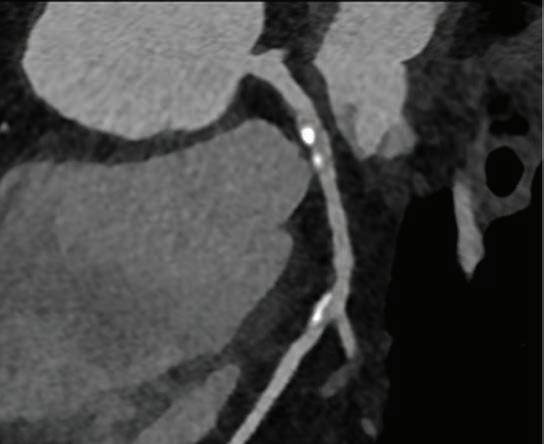

Photon Counting CT

Believe your eyes!

Conventional high end CT

Diagnosis = > 50% stenosis

Diagnosis = minor irregularity only

Photon Counting CT eliminates calcium blooming artefact therefore lessens unnecessary referrals for invasive angiography by up to 50% (e.g. Simon J, J Cardiovasc Comput Tomogr. Jan-Feb 2024 and Zsarnoczay, E. Eur Journal Radiol April 2023)

Dose equivalent = 6 Chest X-ray exams

Dose equivalent = 1 Chest X-ray exam

Photon Counting CT has a revolutionary new detector exquisitely sensitive to X-rays and impervious to electronic noise, making CT at a CXR dose finally a reality (e.g. Dettmer, S. Respiration 2024 and Wassipaul, C. The Lancet Oct 2023)